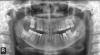

Maria1304 Опубликовано 6 июля, 2012 Поделиться Опубликовано 6 июля, 2012 (изменено) Добрый день!Постараюсь кратко - после пломбирования каналов в 4 и 5 ниж. прав. зубах длительно сохранялась боль. Пломбировочный материал (эндометазон) был выведен за верхушку и как мне объяснил врач, что нижнечелюстной канал очень широкий, нерв близко отсюда и боль, но со временем эндометазон рассосется.10 сеансов лазера не помогли, направили к хирургу-стоматологу, который сделал 6 уколов гидрокортизона в десну, после чего (через 10 дней) образовалось болезненное уплотнение на десне в этом месте, которое он разрезал и поставил дренаж на 5 дней. Сейчас прошло 3 недели, боли стали меньше и реже, уплотнение почти прошло. Хирург сказал пока ничего не делать и придти через 3 мес. на повторный курс. Я сделала панорамный снимок и вижу, что пломбиров. материал как был, так и остался на том же месте, а вокруг затемнение. Вопрос: это затемнение (гранулема, киста?) образовалось в результате выведенного материала или, наоборот, материал попал туда из-за того, что там уже было такое состояние? И правильная ли тактика лечения? Не будет ли хуже через 3 мес.? И еще вопрос: нужно ли удалять ретенированные 8-е зубы если они не беспокоят? Возможно они в таком положении уже очень давно, ортопантомограмму делаю первый раз и не знаю как было раньше. Мне 49 лет. Спасибо за внимание. Жду ответов. Изменено 6 июля, 2012 пользователем Maria1304 Ссылка на комментарий

ger_berra Опубликовано 6 июля, 2012 Поделиться Опубликовано 6 июля, 2012 (изменено) В области верхушки 4 зуба есть деструкция (разрушение) костной ткани.Погрешности в обработке корневых каналов,выведение НЕ МАТЕРИАЛА,А ИНФИЦИРОВАННОГО СОДЕРЖИМОГО КАНАЛА провоцирует боль.И восстановление зуба в Вашем случае -позавчерашний день.Коронка должна быть,а не пломба на гвозде.Никакие уколы в десну не помогут,даже не надейтесь.Возможно дадут кратковременное улучшение.Каналы надо перелечивать.Только к другому доктору идите,специализирующемся на лечении каналов.Нижние 8-ки Вам удалять не надо.Они всю жизнь в кости просидели.И вряд ли когда-нибудь прорежутся.Травма будет гораздо больше ,чем польза от такого удаления. Изменено 6 июля, 2012 пользователем ger_berra Ссылка на комментарий